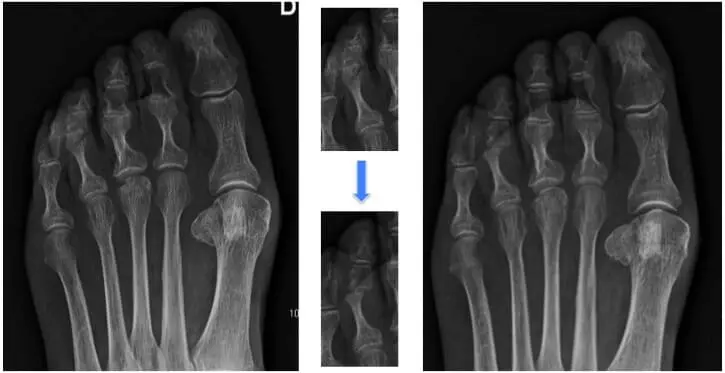

Résection d’un conflit douloureux et saillant (arthroplastie interphalangien)

Fixation de l’articulation douloureuse avec une certaine angulation (arthrodèse)

Ostéotomie de la phalange ou du métatarsien